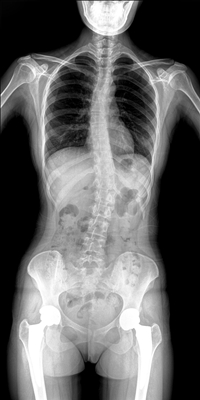

臨床需要對(duì)患者的脊柱情況有全面了解,故而術(shù)前術(shù)后均需要均需要借助DR拍攝X光片便于分析病情、明確診斷及術(shù)后觀察治療效果。大視野動(dòng)態(tài)DR可以對(duì)患者的脊柱進(jìn)行長(zhǎng)尺寸攝影,一次拍攝就能獲取完整的脊柱全景圖像。診斷醫(yī)生通過(guò)拍攝后的影像測(cè)量全脊柱的生物角度、Cobb角等,為脊柱側(cè)彎的畸形矯正患者術(shù)前術(shù)后的檢查提供重要的診斷依據(jù)。

通過(guò)大視野動(dòng)態(tài)DR進(jìn)行全脊柱攝片,其得到的影像密度均勻、清晰、接緣處過(guò)渡自然。且操作更加便捷,不需要二次攝片然后進(jìn)行圖像拼接,拍攝時(shí)間短,效率高。在減少輻射劑量的同時(shí)也能為臨床醫(yī)生帶來(lái)更精確的診斷信息。非拼接影像可保證雙腿測(cè)量(如力線)數(shù)據(jù)的準(zhǔn)確性,有效避免攝影信息的丟失。給手術(shù)醫(yī)生提供準(zhǔn)確的術(shù)前診斷數(shù)據(jù),提高手術(shù)成功率。

綜上所述,大視野動(dòng)態(tài)DR進(jìn)行全脊柱成像能夠清晰的呈現(xiàn)骨關(guān)節(jié)結(jié)構(gòu),可以在全景脊柱圖像基礎(chǔ)上對(duì)角度值進(jìn)行測(cè)量,能夠很好的反映骨骼的真實(shí)比例與長(zhǎng)度,為臨床診斷和治療提供了更精確的數(shù)據(jù),有著重要臨床應(yīng)用價(jià)值。